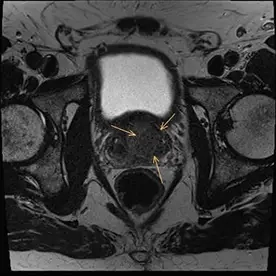

Es erfolgte eine multiparametrische MRT der Prostata mit intravenöser Kontrastmittelgabe. Neben einer Prostatahyperplasie mit ca. 47 ml Volumen zeigte sich der Nachweis von 2 malignitätssuspekten Läsionen.

Die Läsion 1 liegt in der Transitionszone links paramedian basal und im mittleren Drüsendrittel mit einer Signalminderung in T2w (Bild 1), Diffusionsstörung (Bild 2) und Korrelat in der DCE. Die Größe der Läsion beträgt ca. 25x20x28mm, sie zeigt keine Überschreitung der Kapsel und keine Invasion in das neurovaskuläre Bündel (Bild 5). Die Läsion wurde als PI-RADS 5 klassifiziert und hat somit ein sehr hohes Malignitätsrisiko.